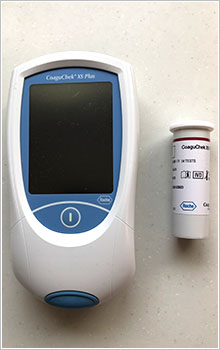

PT-INR測定器

ワーファリンを飲んでいる方には測定が大切です。